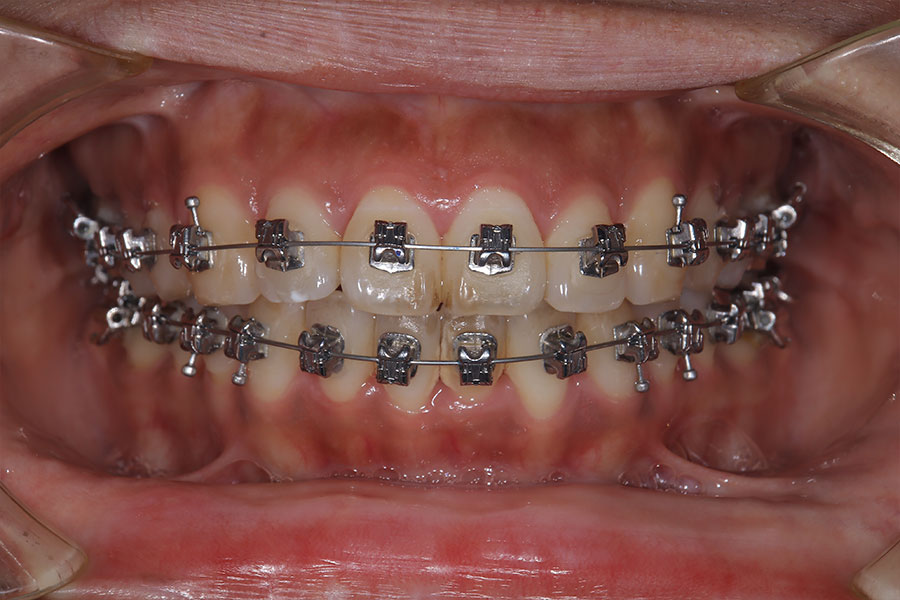

Before -正面-

After -正面-

Before -側面-

After -側面-

| 施術内容 | ワイヤー矯正から、目立ちにくくメタルフリーなインビザラインへ変更しました。 金属アレルギーの不安が軽くなり、取り外しできることで清掃性も向上。見た目も自然で、治療中のストレスが少ない矯正方法です。 |

|---|---|

| 治療期間 | 2年間 |

| 費用 | インビザラインフル 767,800円 リテーナー 30,000円 |

| リスク・副作用 | 治療にともない、歯の破折や歯質の削合、場合によっては抜歯が必要となることがあります。また、金属や補綴物を除去する際に、完全に除去できない場合もあります。 |